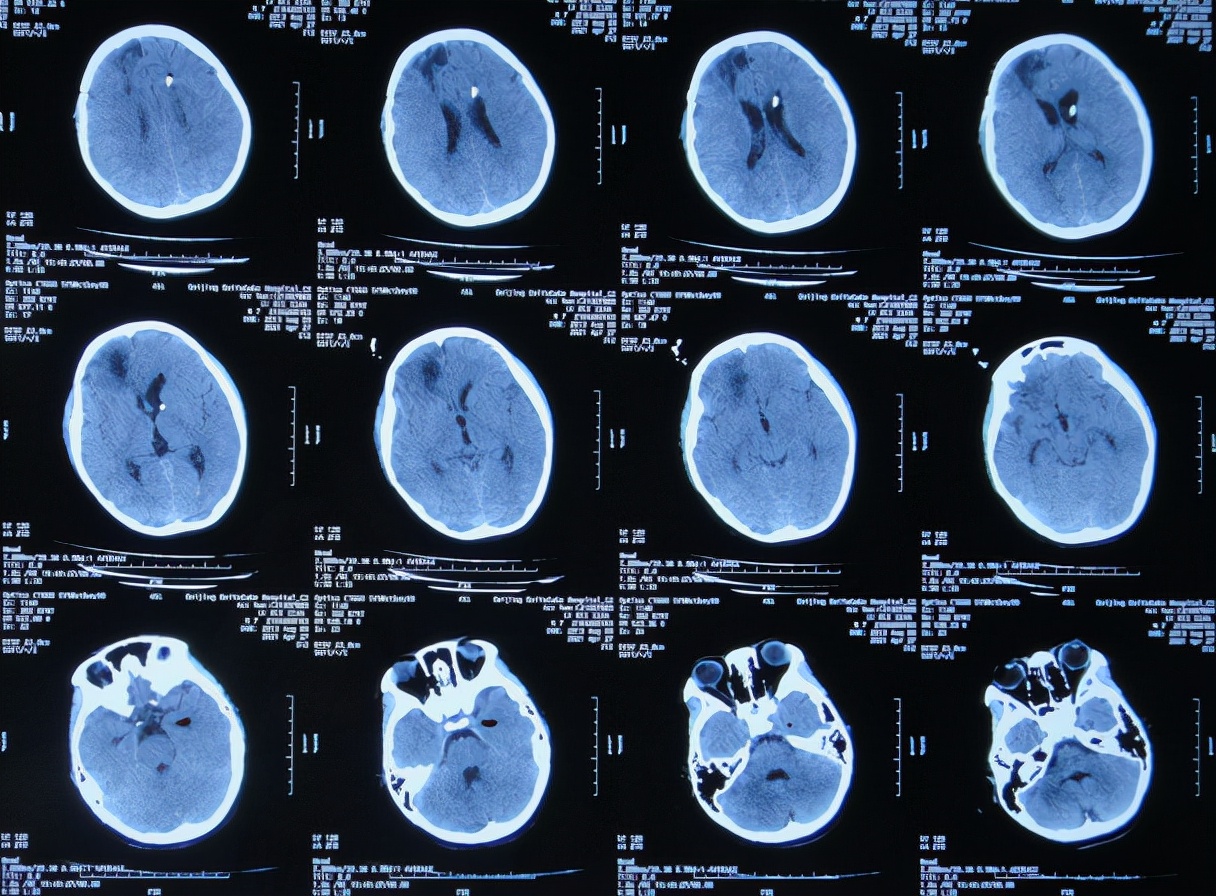

入院当天查脑CT示脑室扩张,硬膜下水肿( 图-8 )。

图-8: 2021年4月27日入院时脑CT